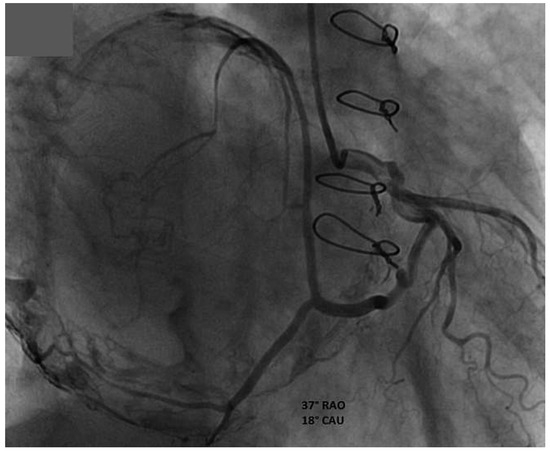

Anterior ST-Elevation Myocardial Infarction After Excimer Laser Extraction of Defibrillator Leads

by Reto Berli, Jürg Grünenfelder and Christophe Wyss

We describe a case of a so far unknown complication after failed extraction of defibrillator leads. Perforation of the LIMA bypass caused by Excimer laser created an arterio-venous fistula from the proximal bypass to the superior subclavian vein and occlusion of the distal [...] Read more.

We describe a case of a so far unknown complication after failed extraction of defibrillator leads. Perforation of the LIMA bypass caused by Excimer laser created an arterio-venous fistula from the proximal bypass to the superior subclavian vein and occlusion of the distal LIMA bypass with consecutive anterior S T-elevation myocardial infarction. Full article